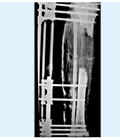

• Example

skin4

Description

Circumferential bone loss of less than 4 cm

4